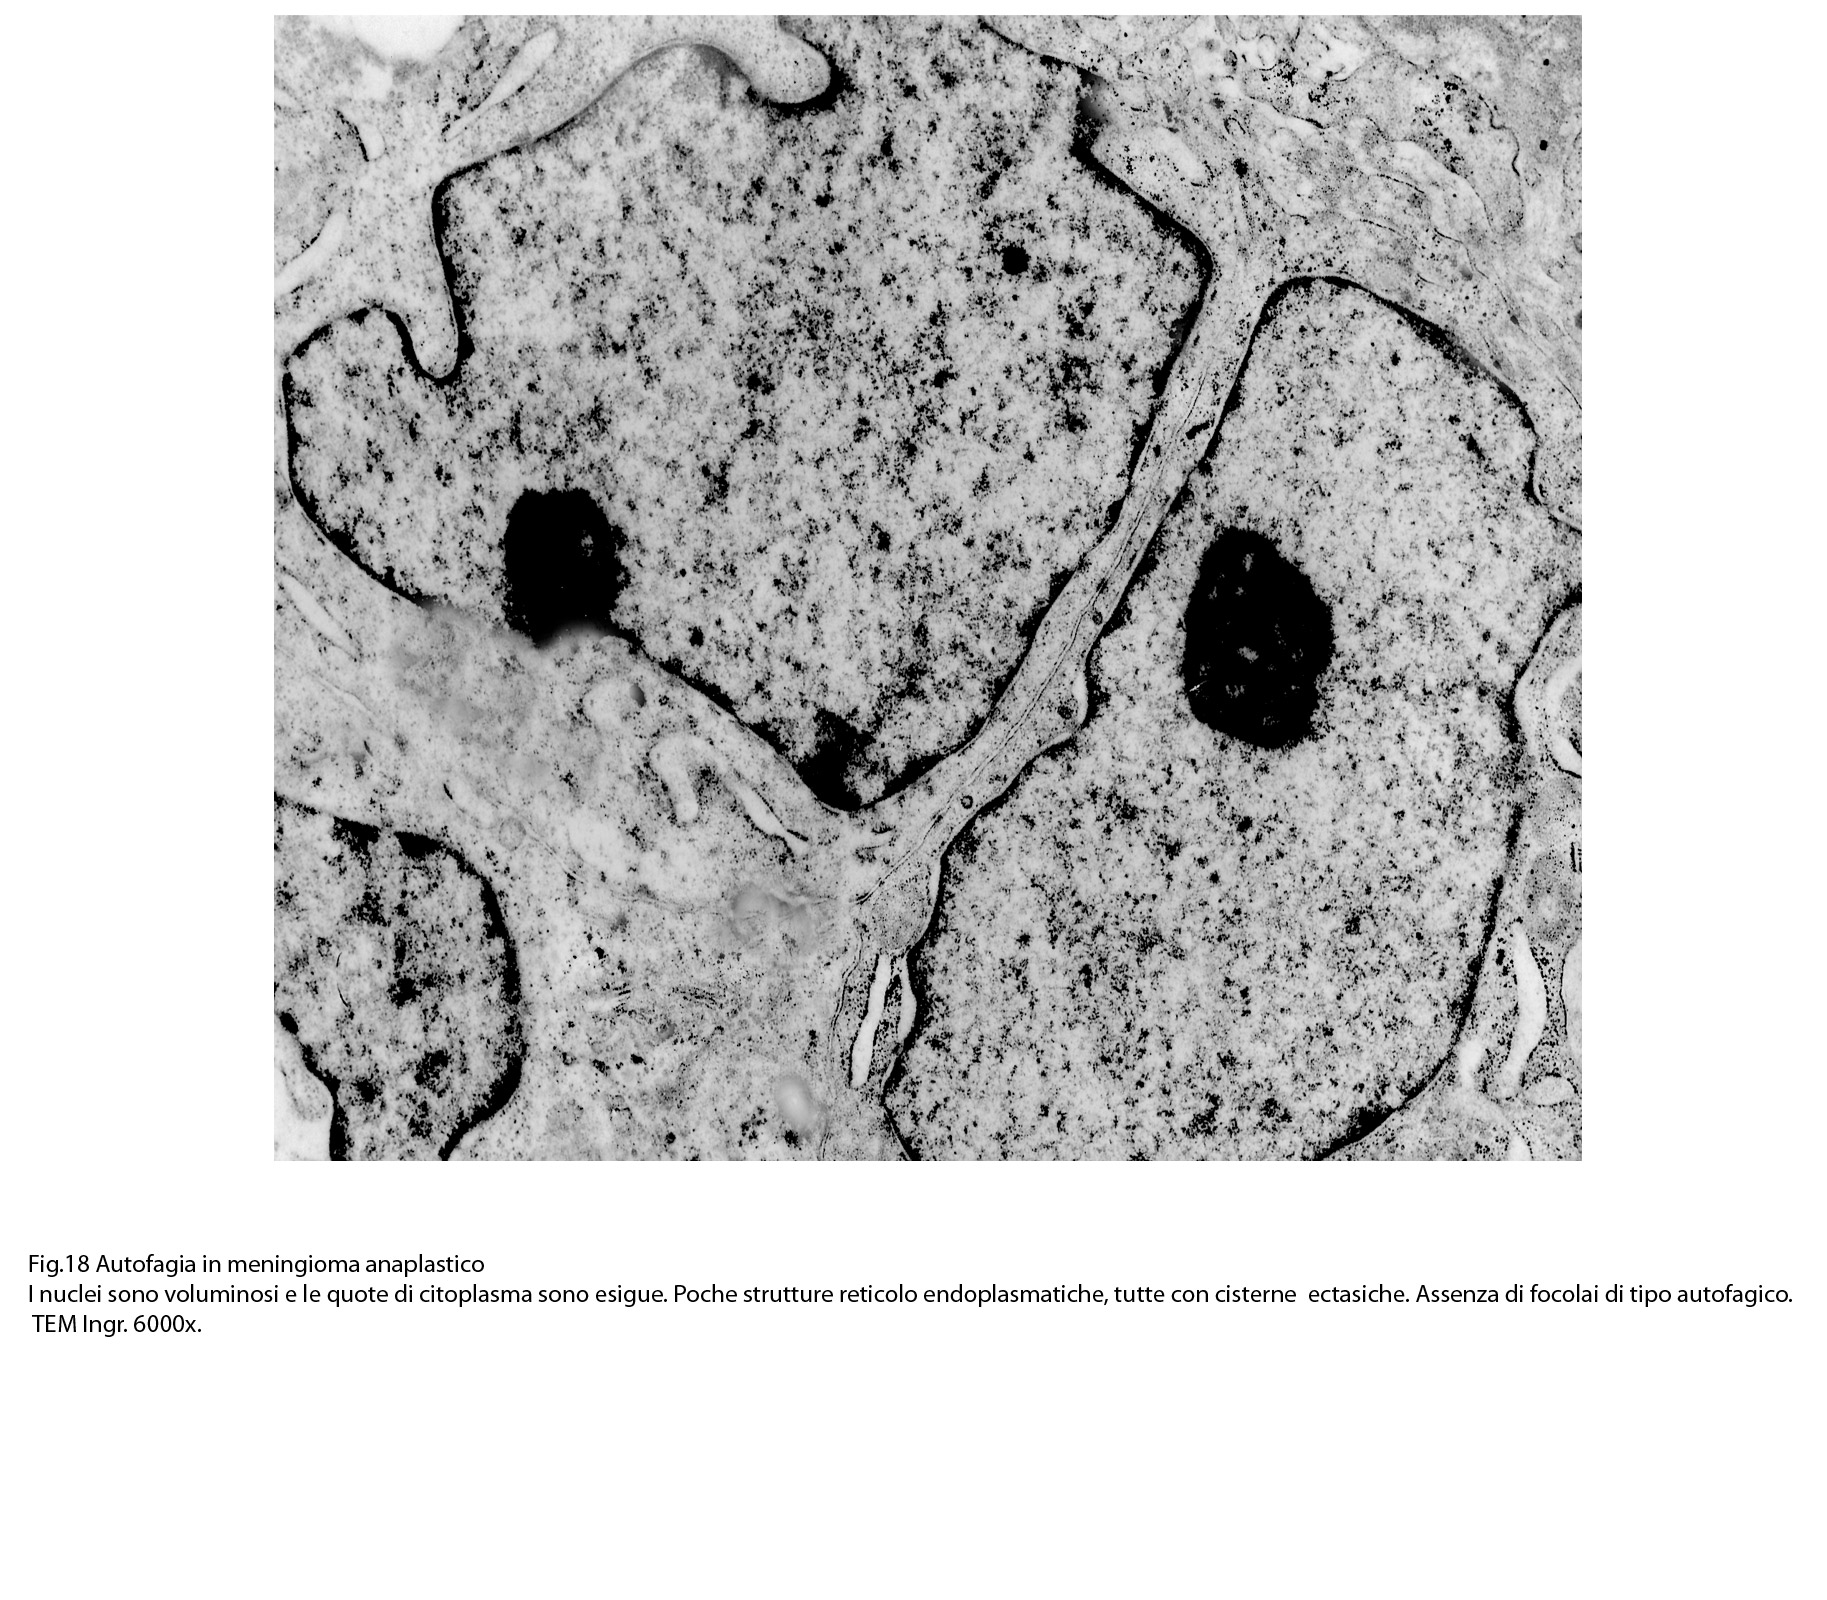

B) FOCOLAI DI AUTOFAGIA IN MENINGIOMI ANAPLASTICI

La popolazione cellulare dei meningiomi anaplastici è data da elementi di piccole e medie dimensioni che si dispongono spazialmente in aggregati informi. Ciascuno di essi ha una forma irregolarmente cuboide o poligonale e soprattutto è caratterizzato da una esigua quota citoplasmatica esigua e da una voluminosa massa nucleare.

Al microscopio elettronico,il citoplasma appare compatto ed il citosol contiene pochi mitocondri, scarso reticolo endoplasmatico ed ergastoplasma, discrete quote di ribosomi liberi e di microtubuli.

Molto frequentemente si riscontrano elementi i quali evidenziano una condizione di cellula binucleata.

Le numerose osservazioni ultrastrutturali condotte su casi di meningiomi anaplastici hanno evidenziato in modo ripetitivo gli abituali caratteri di cellule con tale morfologia e in nessun campo hanno evidenziato focolai riferibili a processi di autofagia.

I reperti dianzi descritti e documentati indicano la esistenza di focolai di autofagia nei meningiomi benigni; reperti questi non riscontrati nei meningiomi maligni. Questi dati, ripetitivi, non trovano a livello morfologico una spiegazione soddisfacente. Se si rimane nel perimetro delle osservazioni descrittive è possibile sottolineare una differenza incontrovertibile: La ultrastruttura del citoplasma dei meningiomi meningoteliali benigni è sostanzialmente diversa da quella dei meningiomi maligni. I primi sono ricchi di organuli e di substrutture e sono frequenti le disfunzioni mitocondriali e lo stress del reticolo endoplasmico, quali fattori avvianti il meccanismo dell’autofagia. Al contrario, i meningiomi maligni sono forniti di quote esigue di organuli (con prevalenza soltanto di microtubuli e ribosomi),e probabilmente non sono esposti a intrinseche disfunzioni o alterazioni endocellulari atte a indurre l’autofagia.